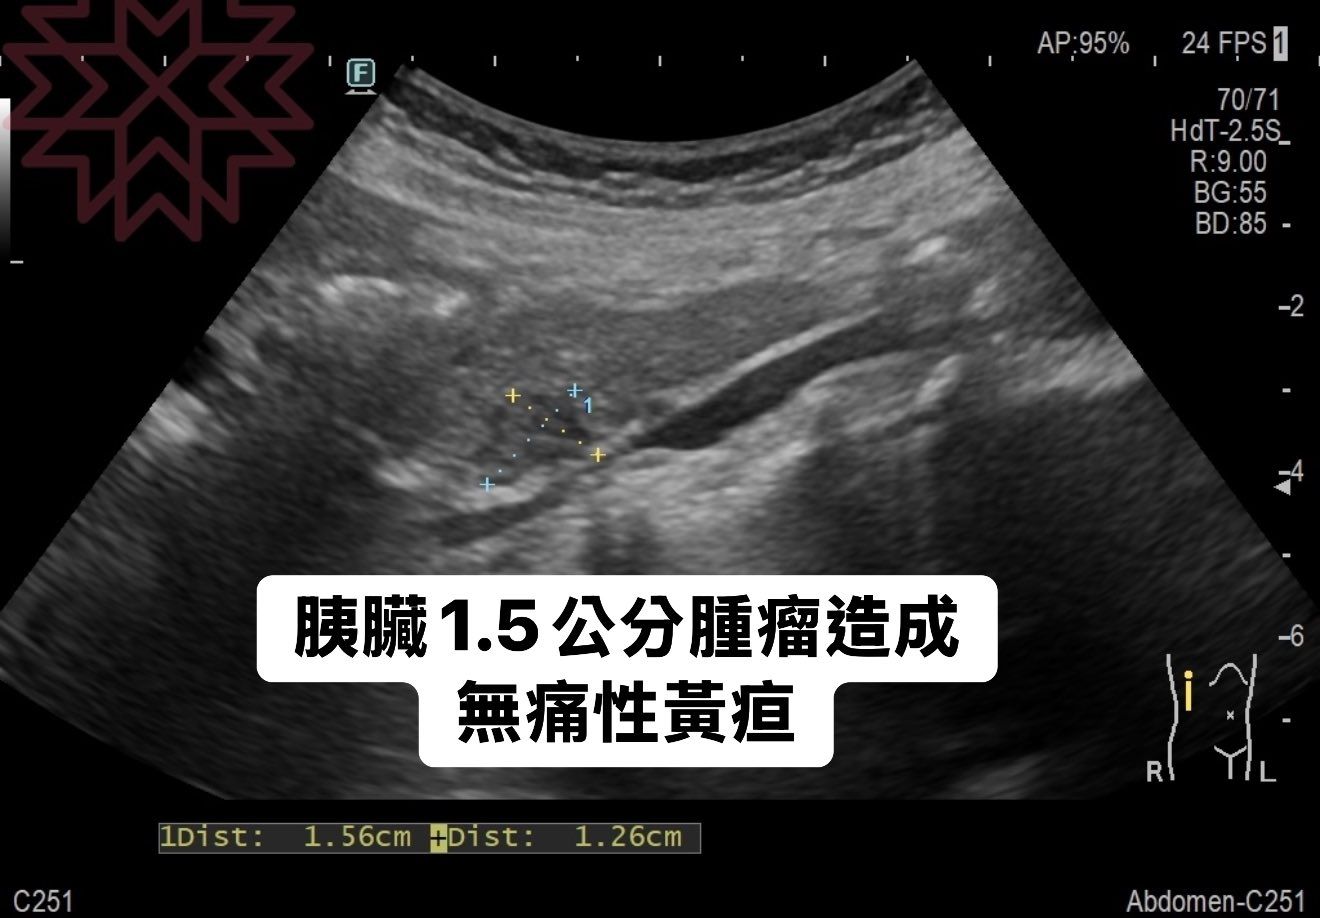

對此,林相宏認為該女患者出現無痛性黃疸,高度懷疑是膽道被腫瘤阻塞所致,馬上為她進行超聲波檢查,發現整個膽道都塞住,膽囊也腫得個水球一樣,最後在胰臟頭部發現一個1.5厘米的腫瘤,高度懷疑是胰臟癌引起的黃疸現象,抽血胰臟癌指標CA199也高達正常的10倍以上460U/ml(正常<37),馬上進行手術評估。

可能是 X 光和顯示的文字是「 F AP:95% 24FPS1 24 FPS 70/71 71 70 HdT-2.5S_ -2. 5S_ R:9.00 BG:55 BG :55 BD:85- 85 BD: -2 膜臟1.5公分腫瘤造成 胰膩 無痛性黃疤 C251 LDist:1.56cmHpist:1.26cm 1.56cm +Dist: 1Dist: 1.26cm R Abdomen-C251 」的圖像